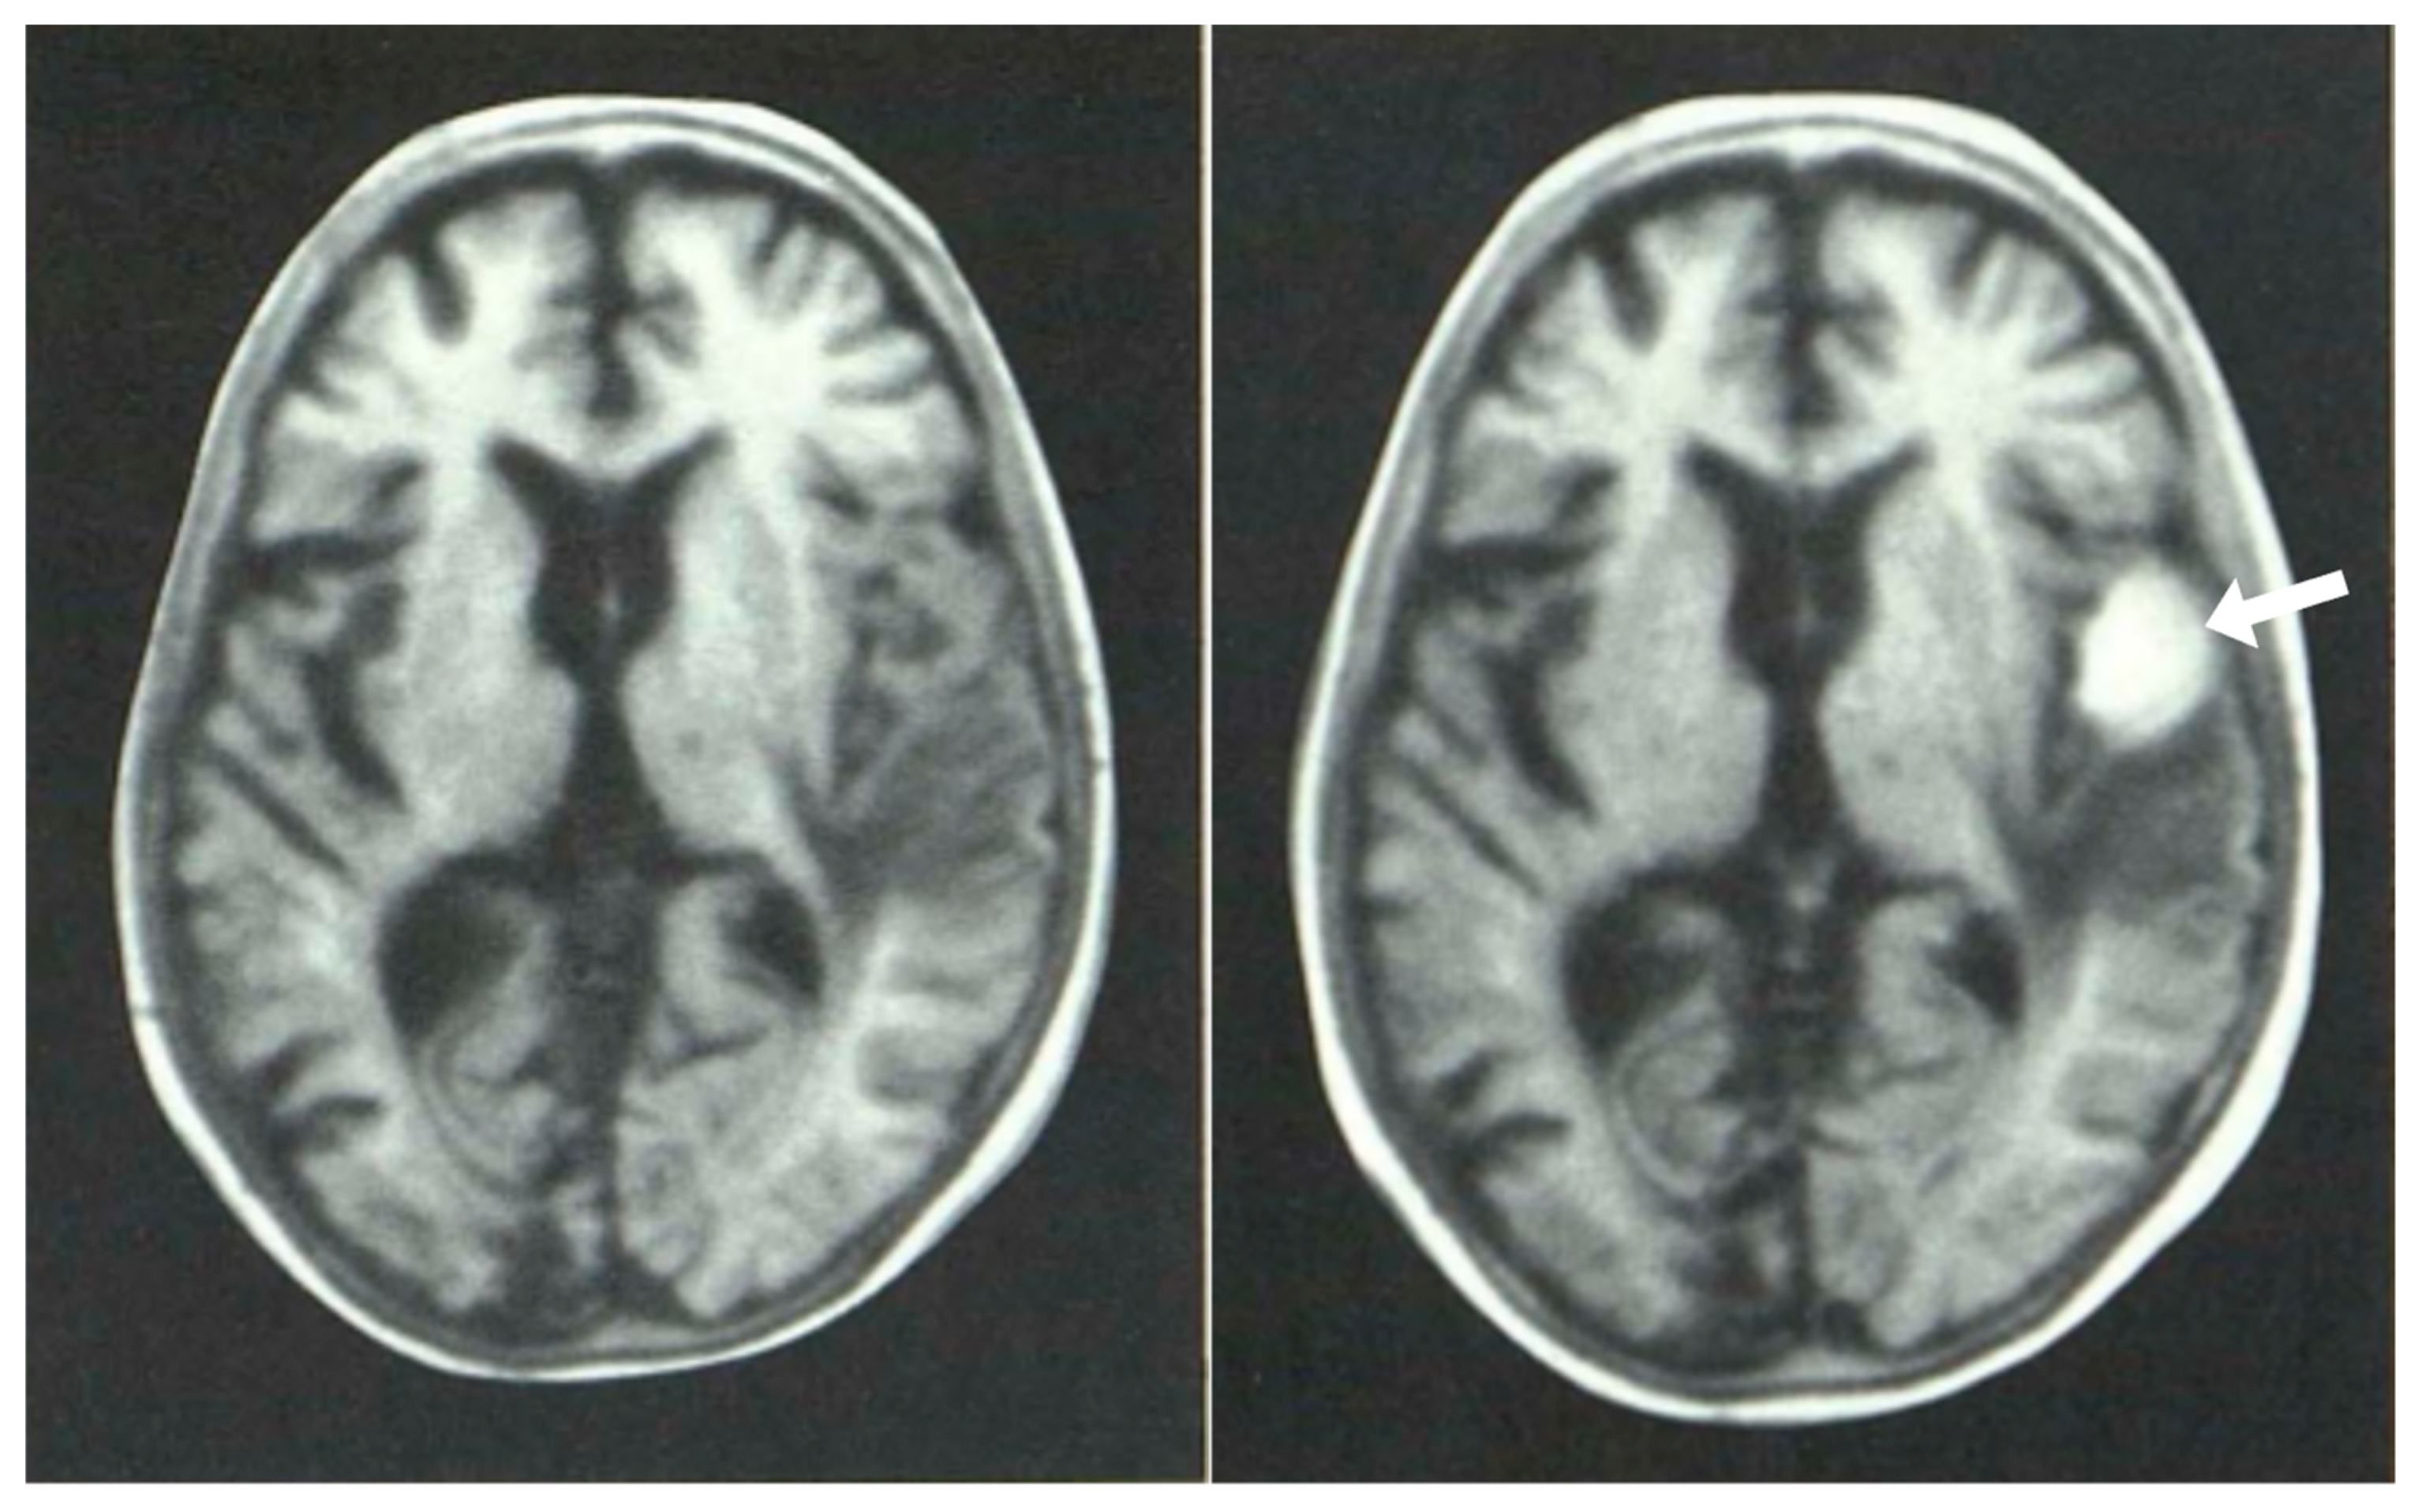

Air studies, frontal views. Normal control (left) and patient with brain tumor in the left cerebral hemisphere (right). The CSF in the ventricular has been replaced by air. The air has a low signal (black appearance) and this creates contrast between the ventricular system and surrounding brain. In the normal air study on the left, the lateral ventricles are symmetrical. In the patient on the right both lateral ventricles are displaced to the right by a tumor in the left hemisphere (black arrow). There is encroachment of the brain into the left lateral ventricle and probable enlargement of the right lateral ventricle.